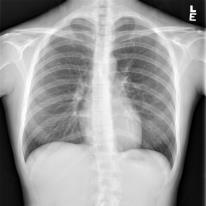

Chest X-ray (CXR) is the most typical radiological exam for diagnosis of various diseases. Due to the expensive and time-consuming annotations, detecting anomalies in CXRs in an unsupervised fashion is very promising. However, almost all of the existing methods consider anomaly detection as a One-Class Classification (OCC) problem. They model the distribution of only known normal images during training and identify the samples not conforming to normal profile as anomalies in the testing phase. A large number of unlabeled images containing anomalies are thus ignored in the training phase, although they are easy to obtain in clinical practice. In this paper, we propose a novel strategy, Dual-distribution Discrepancy for Anomaly Detection (DDAD), utilizing both known normal images and unlabeled images. The proposed method consists of two modules, denoted as A and B. During training, module A takes both known normal and unlabeled images as inputs, capturing anomalous features from unlabeled images in some way, while module B models the distribution of only known normal images. Subsequently, the inter-discrepancy between modules A and B, and intra-discrepancy inside module B are designed as anomaly scores to indicate anomalies. Experiments on three CXR datasets demonstrate that the proposed DDAD achieves consistent, significant gains and outperforms state-of-the-art methods. Code is available at https://github.com/caiyu6666/DDAD.

翻译:切斯特X射线(CXR)是诊断各种疾病的最典型的放射检查;由于昂贵和耗时的注释,发现CXR中异常现象非常有希望;然而,几乎所有现有方法都把异常检测视为单类分类(OCC)问题。它们模拟培训期间仅传播已知的正常图像,并将不符合正常特征的样本作为测试阶段的异常点,因此在培训阶段忽略了大量含有异常点的未贴标签图像,尽管这些图像在临床实践中很容易获得。在本文件中,我们提出了一个新颖战略,即使用已知的正常图像和未贴标签图像来检测非异常点检测(DDDD),使用已知的正常图像和未贴标签图像。拟议方法包括两个模块,即A类和B类。在培训期间,A单元将已知的正常和未贴标签图像作为投入,以某种方式从未贴标签图像中捕捉出异常点特征,而模块B类则只模拟已知的正常图像的分发。随后,A类和B类异点检测模块之间的不易位性(D级)和B类内部的变异性模型显示已设计为稳定的变数。